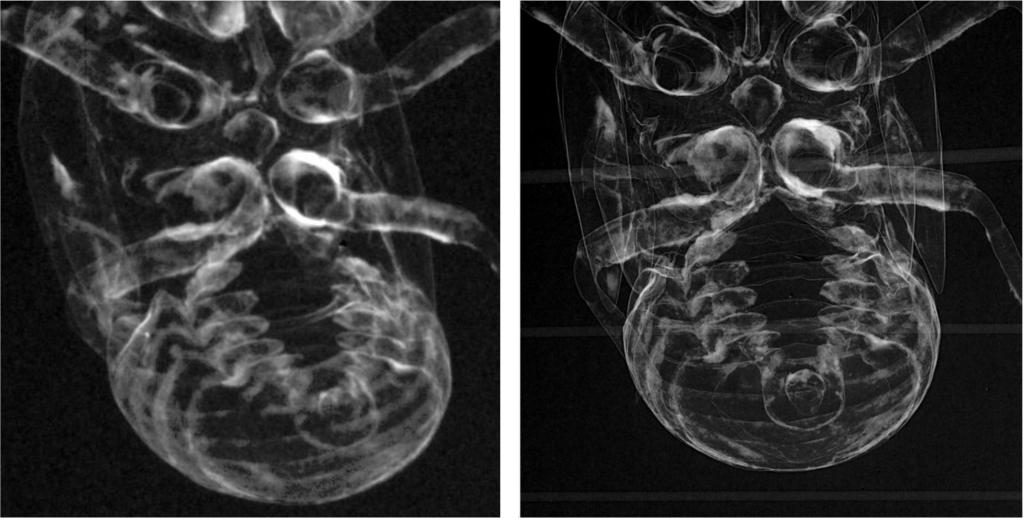

图3 X射线吸收和相位衬度下的蝉蜕图对比